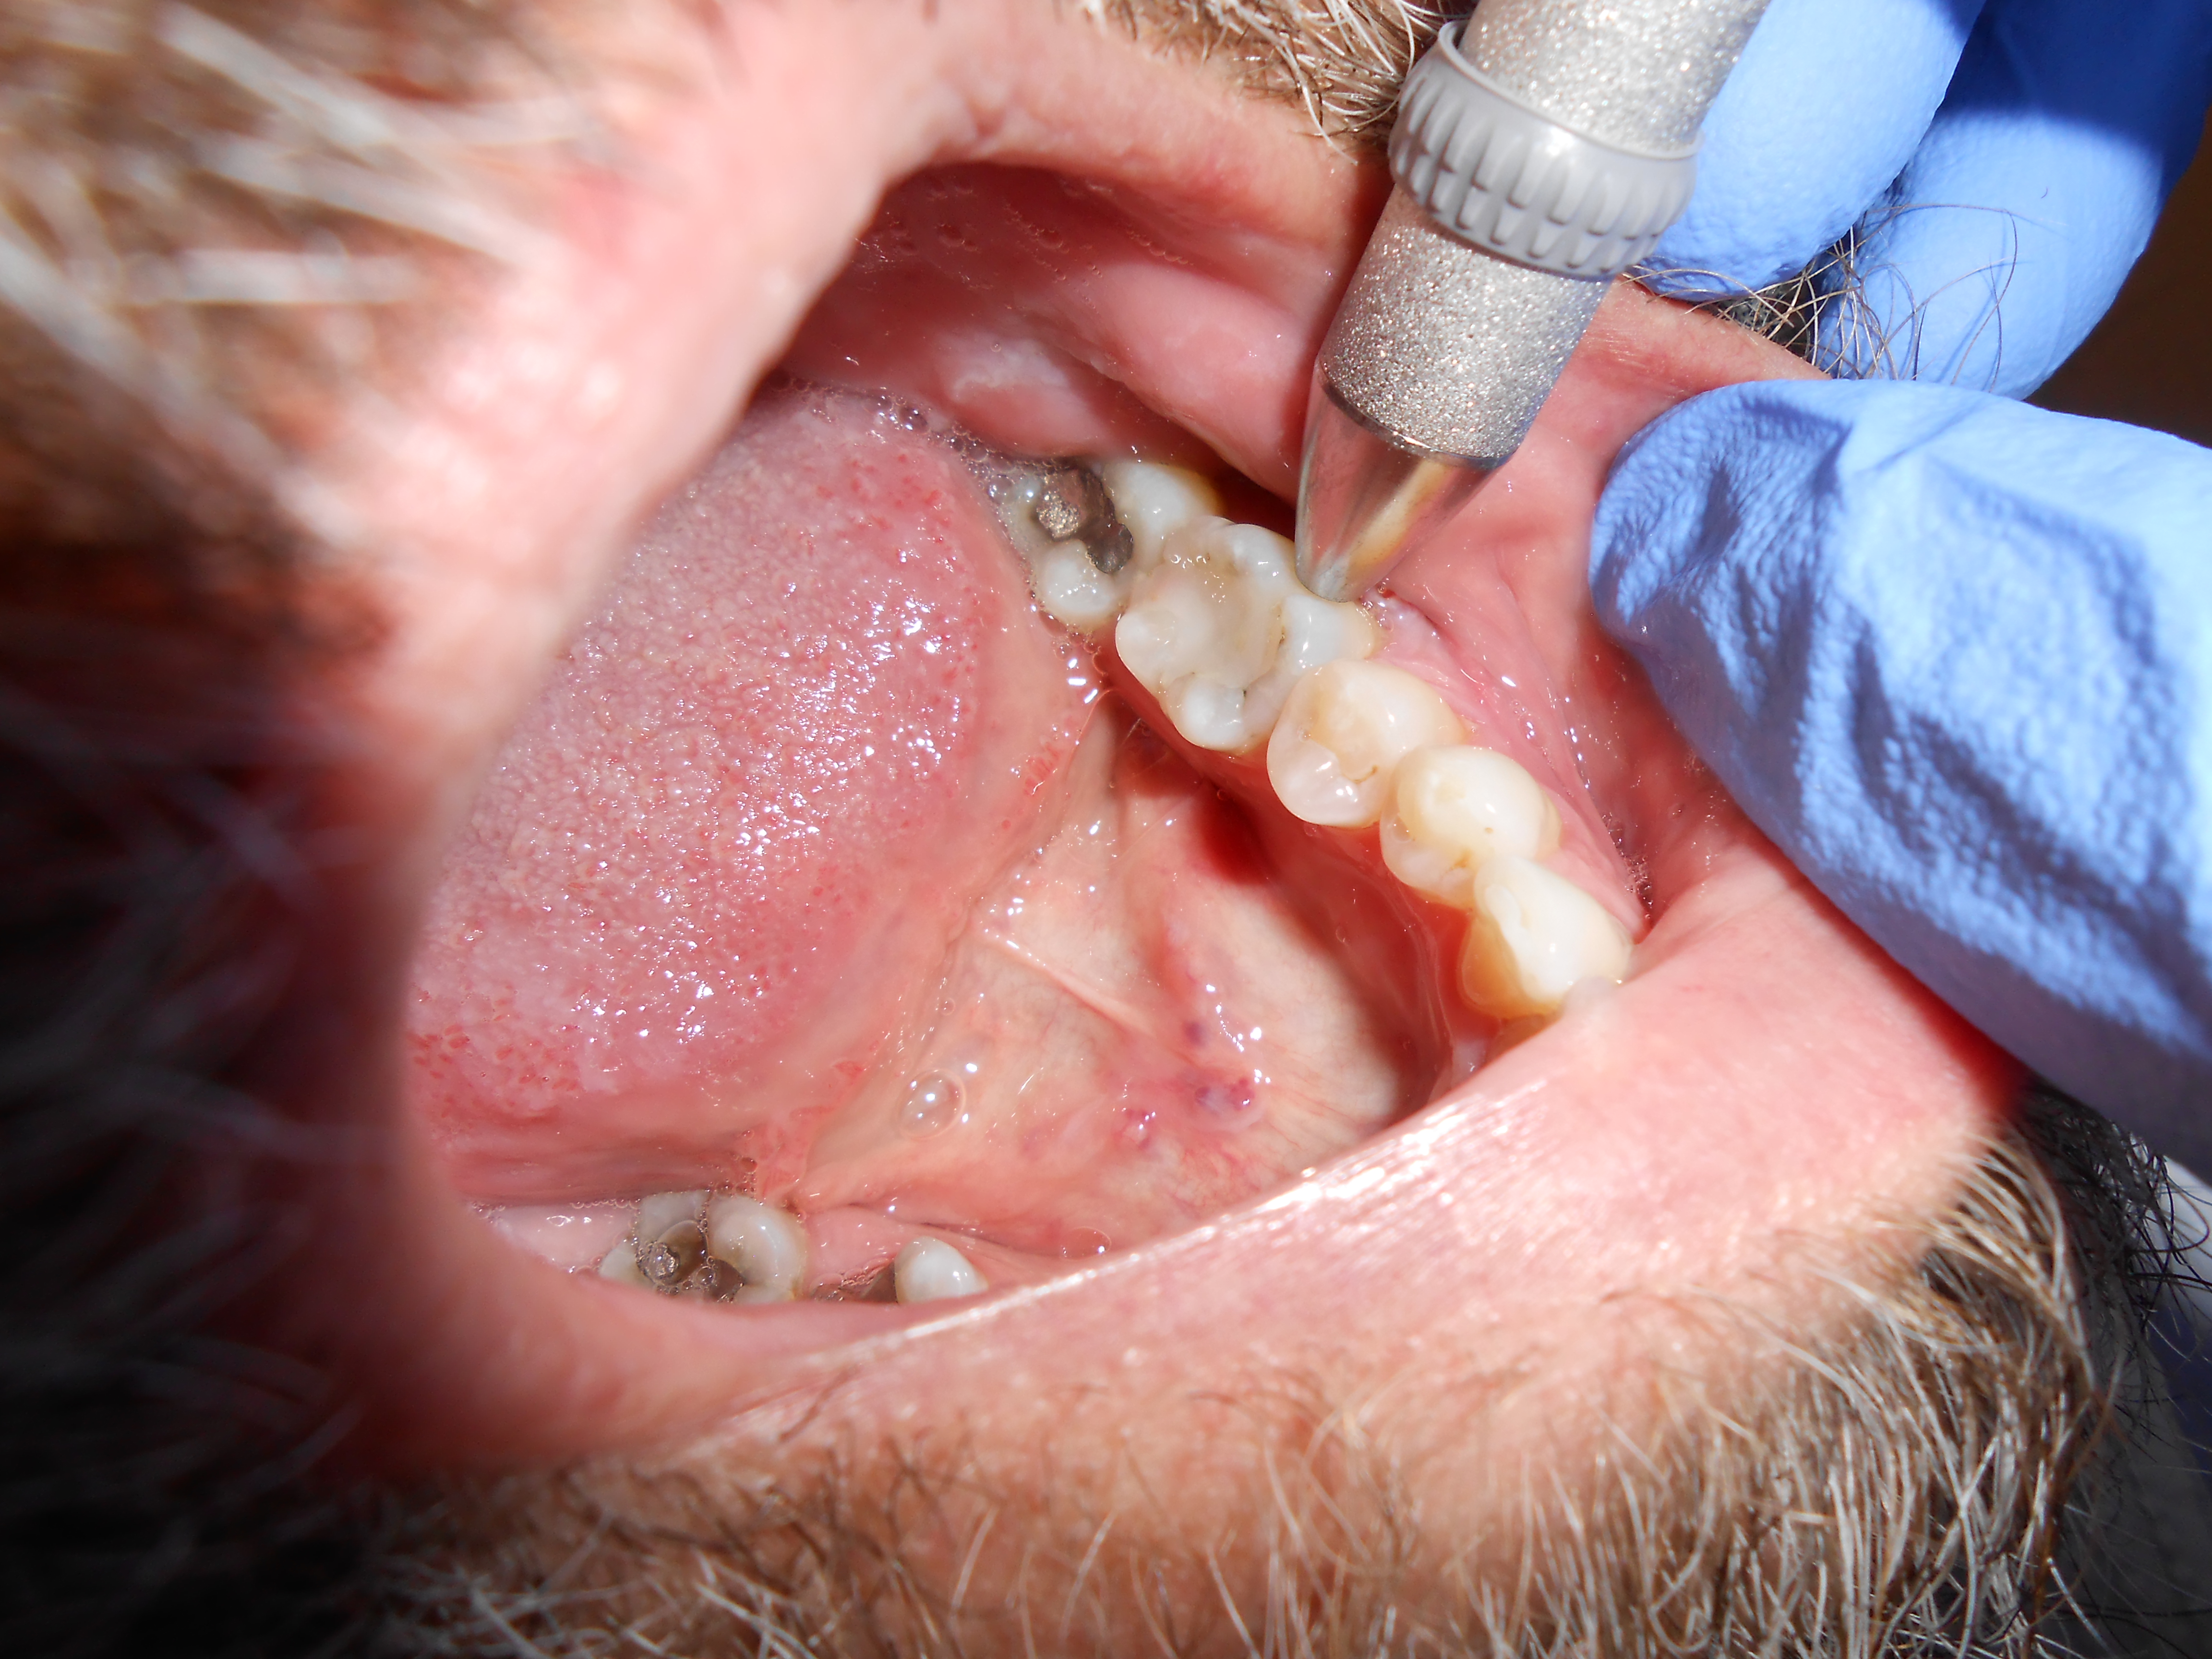

The palpation examination tests for the sensitivity of the gingival tissue and the cortical and medullary bone for infection and/or inflammation (Figure 2). It is important to note that even when there is no radiographic evidence of an apical infection, clinically, an infection may be present. Bender and colleagues5 reported that it is not uncommon to have extensive disease of the bone when there is no evidence on a radiograph.

Palpation testing on tooth No. 19 performed by pressing index finger around the buccal and lingual gingiva.

Figure 2